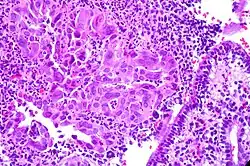

A cervicite é uma inflamação do colo do útero, também conhecido como cérvice uterino.

Cervicite é uma irritação do colo do útero provocada por um número de organismos diferentes. Causas comuns são a gonorréia, herpes, clamidia e infecções bacterianas. Existem também cervicites crônicas comuns nas mulheres depois do parto. É associada também freqüentemente com a gravidez e o uso de contraceptivos orais. Menos geralmente, a cervicite é causada por sensibilidades a determinados produtos químicos, incluindo aqueles nos espermicidas, no látex das camisinhas, e nos tampões vaginais.